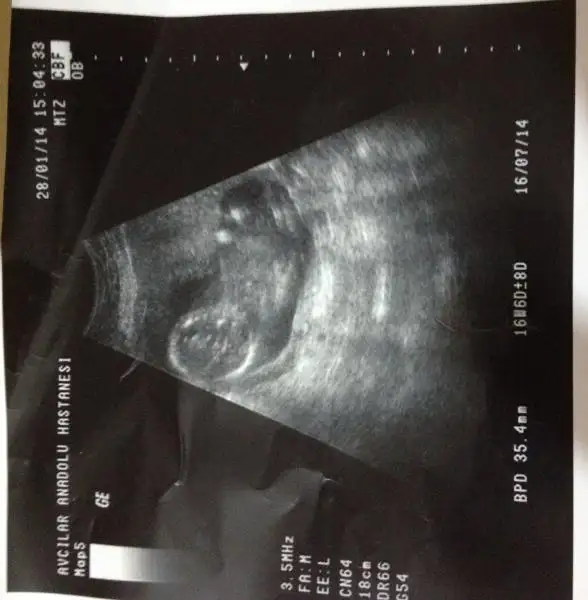

kızlar tecrübeli arkadaşlardan yorum rica ediyorum. doktorum%85-90 erkek dedi. henüz 12. haftamdayım. $2014-02-12 18.18.41.webp

kızlar tecrübeli arkadaşlardan yorum rica ediyorum. doktorum%85-90 erkek dedi. henüz 12. haftamdayım. Eki Görüntüle 977889

şimdiden teşekkür ederim..